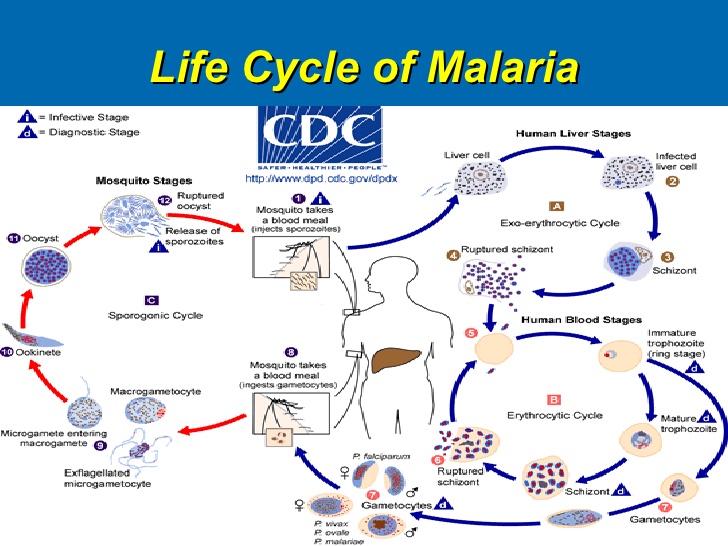

iv. Vectors: Vectors are small organisms ( e.g. insects) that transmit disease- causing organisms from one individual to another. Vectors does not suffer from the disease it transmits e.g. Female Anopheles Mosquito

Life cycle of malaria parasite

iv. Vectors: Vectors are small organisms ( e.g. insects) that transmit disease- causing organisms from one individual to another. Vectors does not suffer from the disease it transmits e.g. Female Anopheles Mosquito

Life cycle of malaria parasite